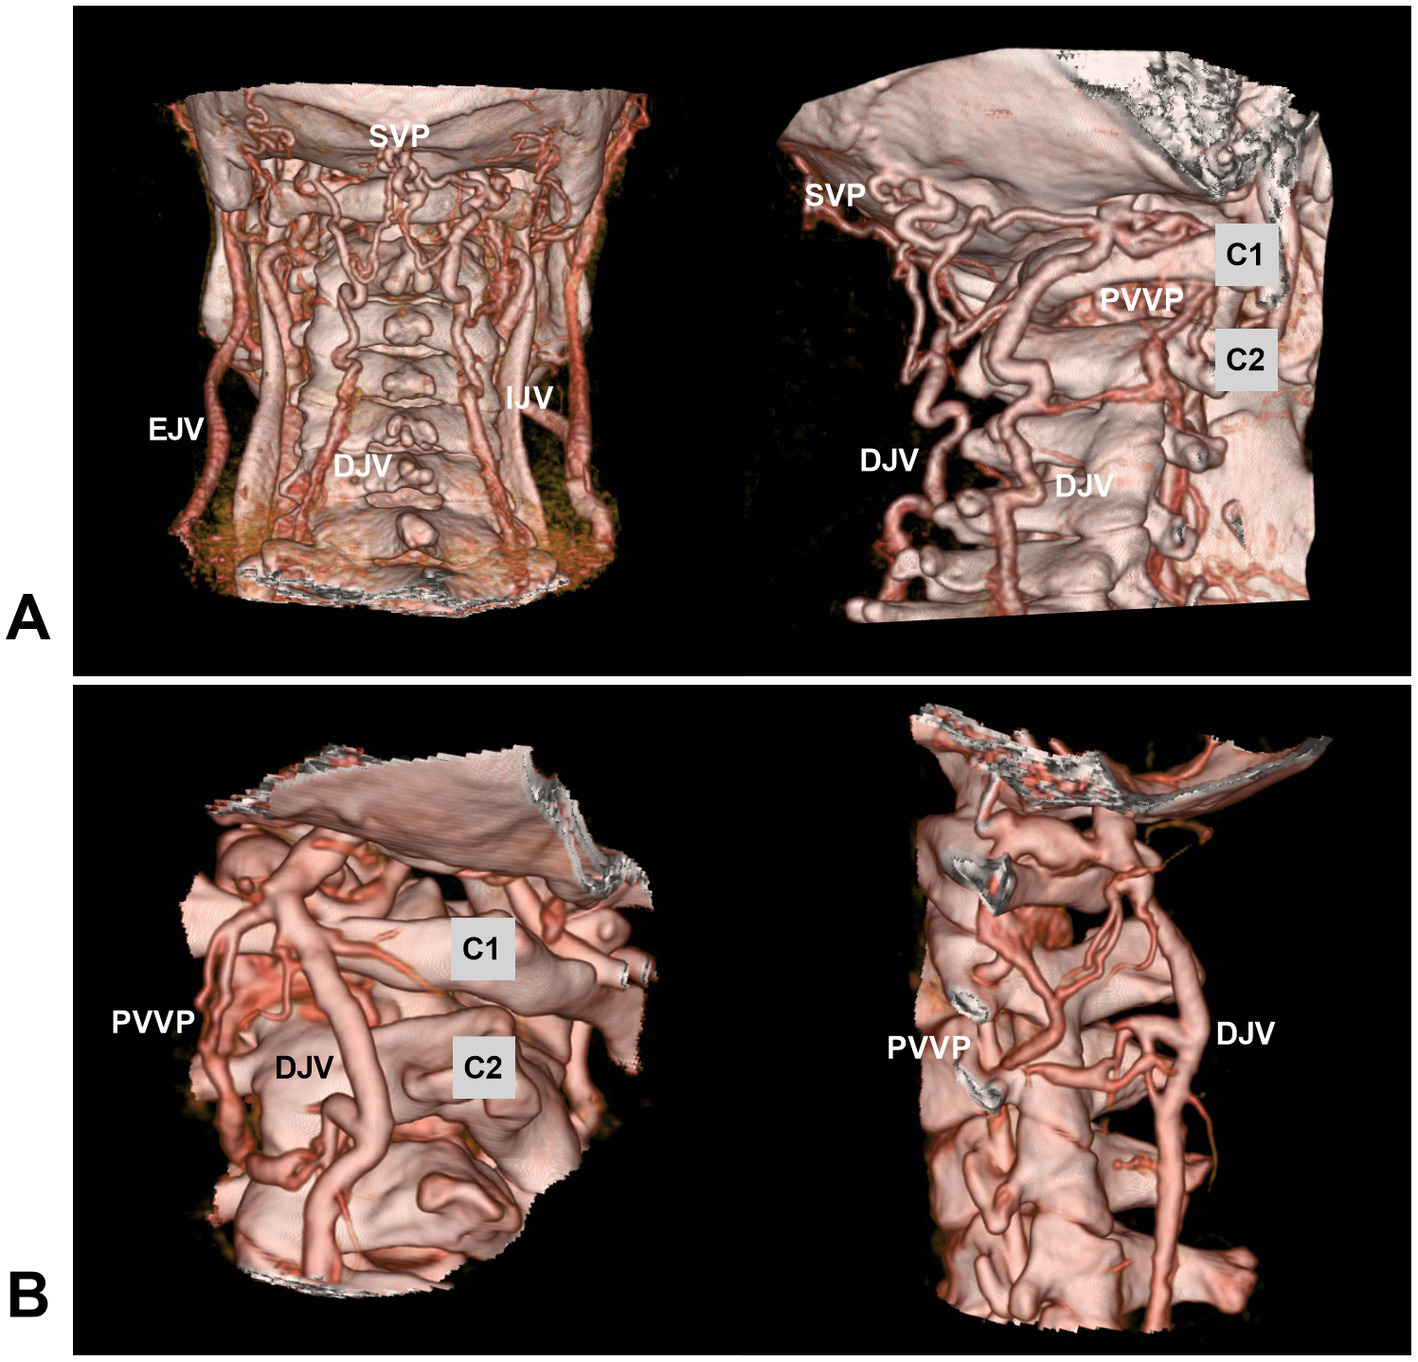

Venous drainage in the high cervical CCJ region is abundant, complex and varied, including the extradural and intradural drainage systems (13, 14, 49, 50). The extradural drainage system includes the anastomosed paravertebral and epidural venous plexuses (38, 51). The paravertebral venous plexus communicates with the deep jugular vein, sigmoid sinus and suboccipital venous plexus (Figure 3) (13, 40, 52). The intradural drainage system includes the veins of the lower brainstem and upper cervical cord and anterior/posterior median/lateral spinal veins anastomosed with the veins of the medulla oblongata (13, 14, 34). In addition, several bridging veins collect drainage from the lower brainstem and upper cervical cord into adjacent sinuses or the venous plexus via the radicular vein along nerve rootlets (13, 34).

Figure 3

Venous plexuses in the CCJ region. (A) Posterior anterior view (left panel) and oblique view (right panel) CTA showing the anastomosed SVP, PVVP, and DJV. (B) Oblique view (left panel) and lateral view (right panel) CTA showing the anastomosed PVVP and DJV. C1, C2, first and second cervical vertebrae; CCJ, craniocervical junction; CTA, computed tomography angiography; DJV, deep jugular vein; EJV, external jugular vein; IJV, internal jugular vein; PVVP, paravertebral venous plexus; SVP, suboccipital venous plexus.